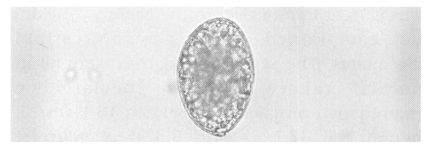

Case 1: A 7-year-old girl visited out-patient clinic on July 27, 2000, due to spontaneous discharge with the chain of segments which was 42 cm in length (Fig, 1). She had no history of eating raw fish except once when she ate raw salmon flesh all together with her parent and sister in January, 2000, in Sockcho-shi, Kangwon-do, Korea. The salmon was caught from a river in the vicinity. She did not complained of any gastrointestinal discomfort. The serum chemistries were all in normal ranges and the hematologic examination revealed; hemoglobin 13.1 gm/dl, hemotocrit 37.5%, WBC 8.400/µl, platelet 3,400 × 103/dl, MCV 85.9 fl, MCH 29.9 pg, total eosinophil count 200/µl. The coprological study was positive for D. latum eggs (Fig. 2). The worm was identified as D. latum, based on the biological characters: external morphologies, coiling of uterus, number of uterine loops, position of genital opening, mor-phologies of cirrus, cirrus sac and seminal vesicle, position of vagina and uterine pore (Fig. 3). A single dose of praziquantel 400 mg was given but stool examination was still positive a week later. Another dose of 600 mg was given to and the young female patient was found to be free from the egg after one month.